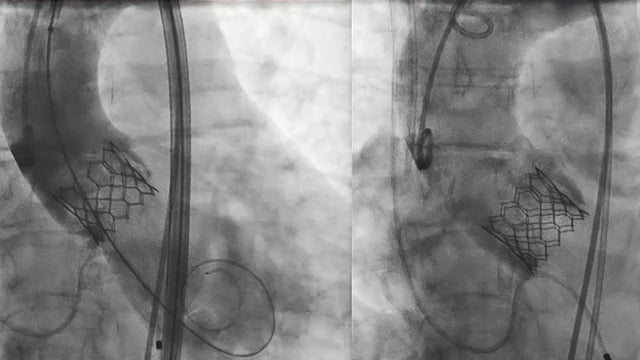

Transcatheter valve-in-valve intervention: LIVE Educational Case from The Prince Charles Hospital, Metro North Health - Brisbane, Australia

Review a live educational case from The Prince Charles Hospital focused on transcatheter valve-in-valve intervention, highlighting anatomical challenges, critical CT imaging roles, and meticulous planning to prevent complications and ensure favorable outcomes.